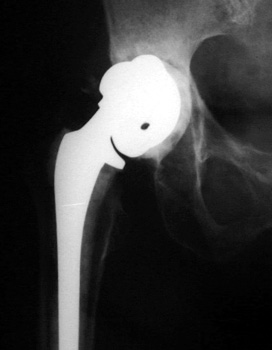

No prior studies available. Abnormally widened interfaces surrounding entire cement mantle of femoral component, consistent with loosening.

LOOSENING